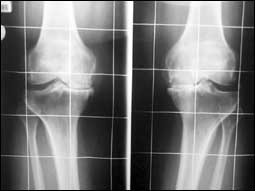

خشونة الركبة بين الأسباب والوقاية والعلاج

احتكاك وتآكل مفصل الركبة من الموضوعات المهمة التي تؤرق الكثير من الناس وخصوصاً كبار السن منهم، حيث يبدأ الألم الناتج عن اهتراء الغضاريف في ازدياد مستم.........